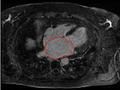

File:LASegAxialView.png

LASegAxialView.png (610 × 460 pixels, file size: 45 KB, MIME type: image/png)